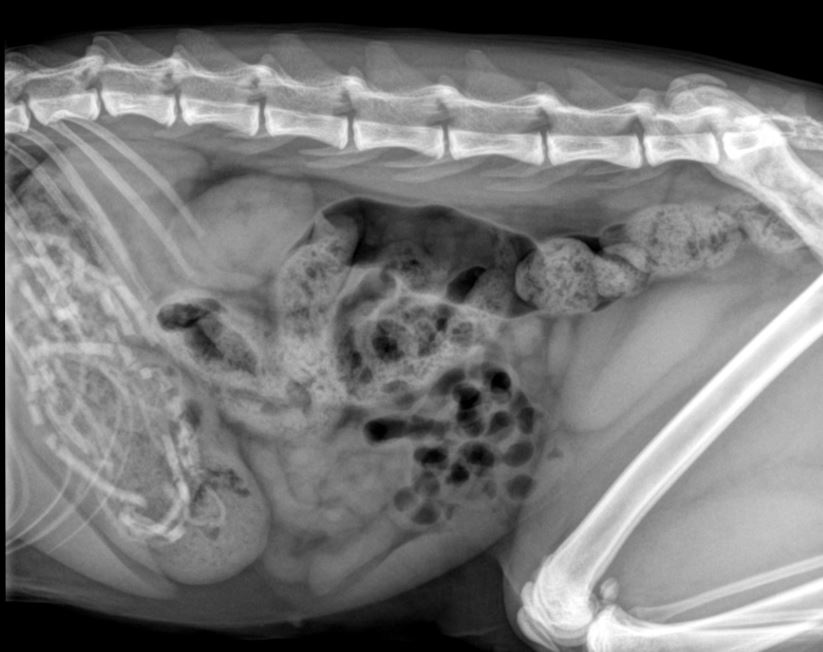

She rushed the cat to Shipston Vets in Shipston-on-Stour, which is part of the VetPartners family of practices, where an examination and X-ray discovered that Winnie had a ball of tangled elasticated bands inside her stomach.

“Winnie was brought in to see us because she was quieter than usual and had started vomiting. Then her owner found two hairbands in Winnie’s poo and became worried that she may have swallowed more. We could feel something firm in her stomach, so we performed an X-ray and this revealed that there were quite a few bands inside Winnie.

“It was important they were removed as soon as possible, so I performed surgery to access her stomach and I couldn’t believe it when we counted 21 hairbands. They had become tangled together and created a big clump that was causing a partial blockage, which is what had caused the vomiting and stomach upset.